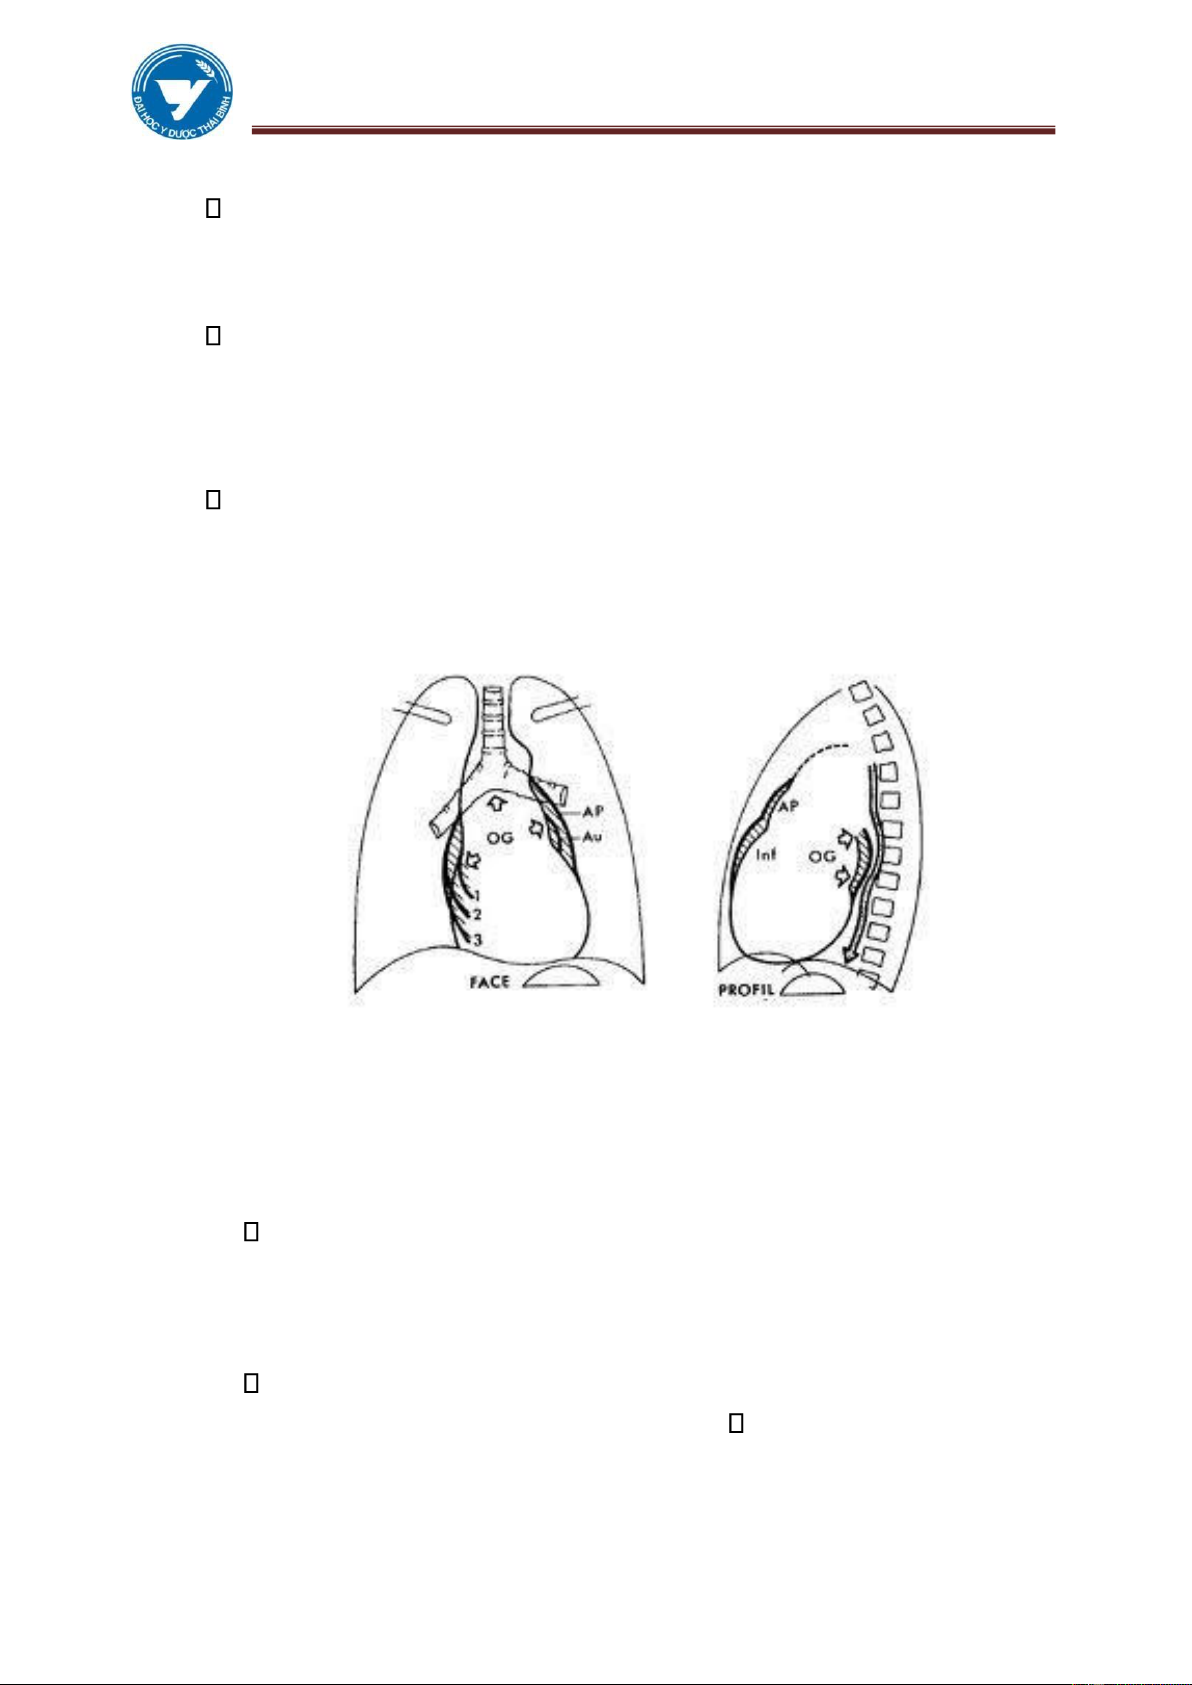

Hình 3.6 Bóng tim bình thường

Hình 3.7 Bóng tim lớn từng buồng lOMoAR cPSD| 61301459

Hình 3.8. Bóng tim lớn toàn bộ